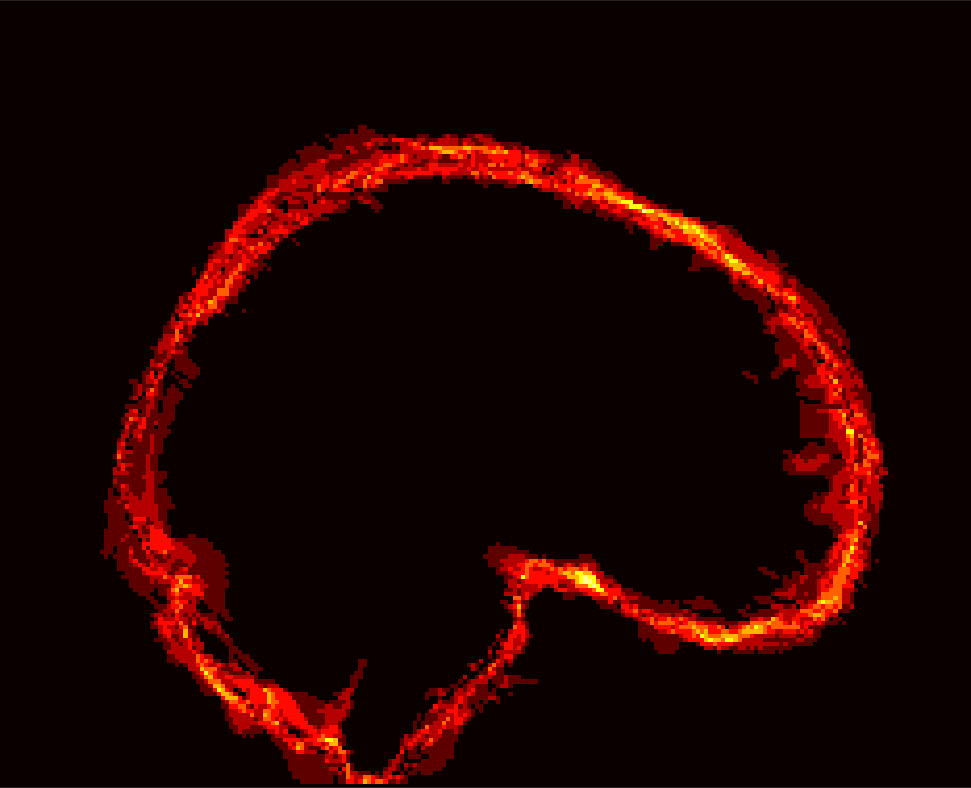

Fig. 1 shows example images from each dataset to illustrate image variability. IBSR and LPBA40 contain images from normal subjects and include large portions of the neck; BRATS has very low out-of-plane resolution; and the TBI dataset contains large pathologies and abnormal skulls.

Refer to caption

Figure 1: Illustration of image appearance variability on a selection of images from each (evaluation) database. From top to bottom: IBSR, LPBA40, BRATS and TBI.